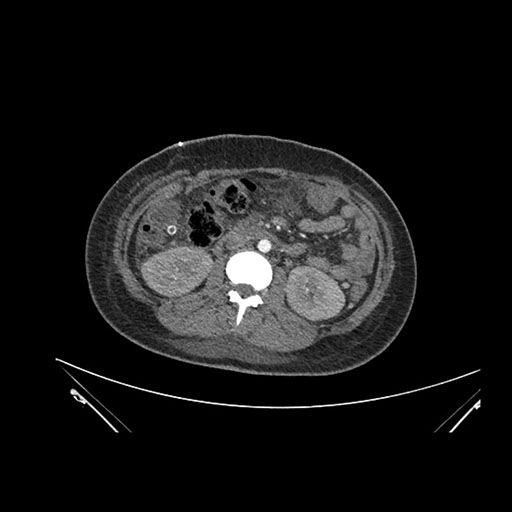

Coronal Venous